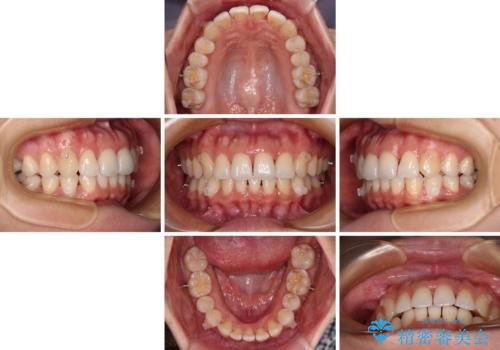

捻れた前歯をインビザラインで整える

- 捻れた前歯が飛び出しており、口が閉じにくいとのことで来院された患者様です。

出っ歯というわけではないものの、前歯の捻転により口唇が押し出されている状態でした。

親知らずを抜去し、歯列全体を後方に移動させつつ、IPR(歯と歯の間を削る)でスペースを獲得し、インビザラインを用いて叢生を解消しながら前歯の突出を改善することとしました。

骨格的に上下正中がずれていたため、奥歯がしっかりと噛み合うか心配でしたが、ずれているなりに、しっかりとした咬み合わせとなりました。